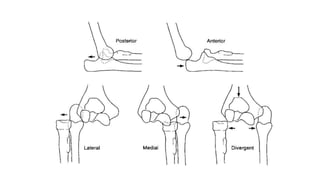

BASED ON DIRECTION •POSTERIOR • POSTERIOMEDIAL • ANTERIOR • LATERAL • MEDIAL

BASED ON DIRECTION

• POSTERIOR

• POSTERIOMEDIAL

• ANTERIOR

• LATERAL

• MEDIAL